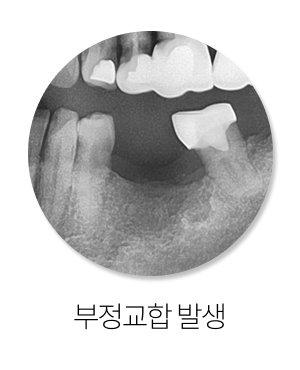

둘째, 맞물림이 흐트러집니다.

한두 개 치아의 기울어짐으로 끝나는 것이 아니라

전체 교합이 어긋나면서 씹는 패턴 자체가 달라질 수 있습니다.